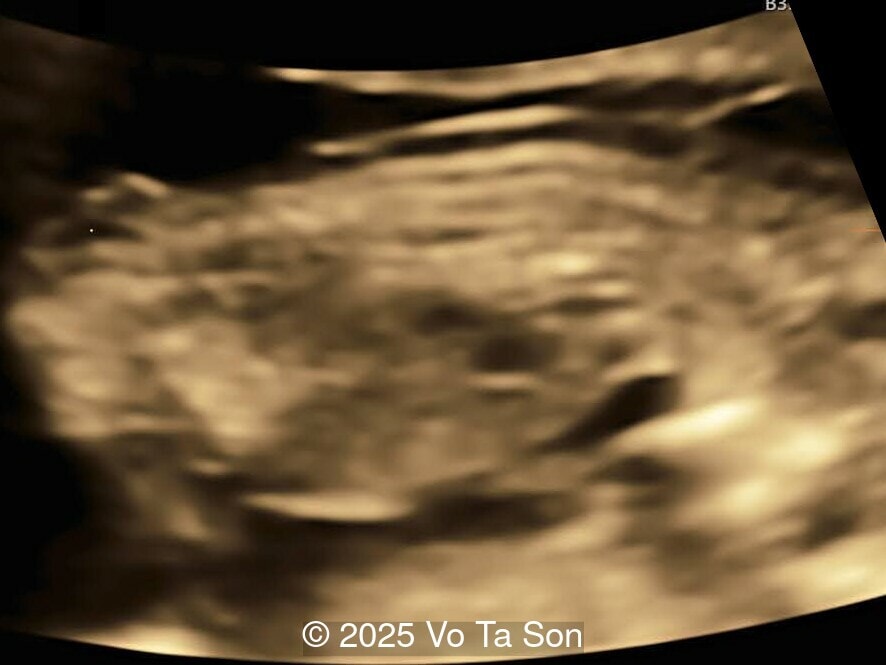

A woman underwent routine prenatal screening at 13 weeks. The non-invasive prenatal test (NIPT) showed low risk for common aneuploidies including trisomy 21, 18, and 13. However, first-trimester anomaly scan revealed multiple fetal anomalies.

Please describe the abnormalities and provide a syndromic diagnosis that best fits the presentation.